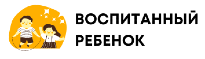

Врожденные пороки сердца делят на 2 группы: белые и синие.

При белых, или бледных, порока сердца, не происходит смешивание артериальной и венозной крови. К белым порокам относят: дефект межпредсердной перегородки, дефект межжелудочковой перегородки, АВ-коммуникацию, сужение (стеноз) легочной артерии, аортальный стеноз, коарктацию аорты, пр.

Белый порок сердца у новорожденных, как правило, ничем себя не проявляет. По мере взросления у детей с белыми пороками сердца появляются клинические симптомы: бледность кожи, повышенная утомляемость, одышка, отставание в физическом развитии.

Испытывая постоянные перегрузки сердечная мышца с годами изнашивается – сердечная недостаточность прогрессирует: появляются отеки ног, увеличивается печень, пр. Без операции продолжительность жизни у людей с белым пороком сокращается на 20-25 лет.

Следует подчеркнуть, что наличие белого врожденного пороки не всегда провоцирует хроническую сердечную недостаточность. Чтобы порок проявил себя, он должен быть гемодинамически значимым – дефект сердечной структуры должен быть весьма значительным. Например, дефект межпредсердной перегородки менее 1 см (гемодинамически незначимый) в большинстве случаев не проявляет себя в течение всей жизни.

При синих пороках сердца происходит смешивание артериальной и венозной крови. Примеры синих врожденных пороков сердца: комплекс Эйзенменгера, полная транспозиция магистральных сосудов, тетрада Фалло, аномалия Эбштейна, пр.

Типичный симптом синего порока сердца – голубовато-серый, или синюшный, цвет кожи (цианоз кожи)из-за дефицита кислорода в крови. Все синие пороки сердца гемодинамически значимые; цианоз кожи хорошо виден сразу после рождения ребенка.

Из-за выраженной гипоксии органов и тканей синие врожденные пороки сердца значительно опаснее белых пороков – без хирургической коррекции ребенок может умереть в первые дни и месяцы после рождения. Пациенты с синими пороками без операции живут на 30-50 лет меньше, чем здоровые люди.